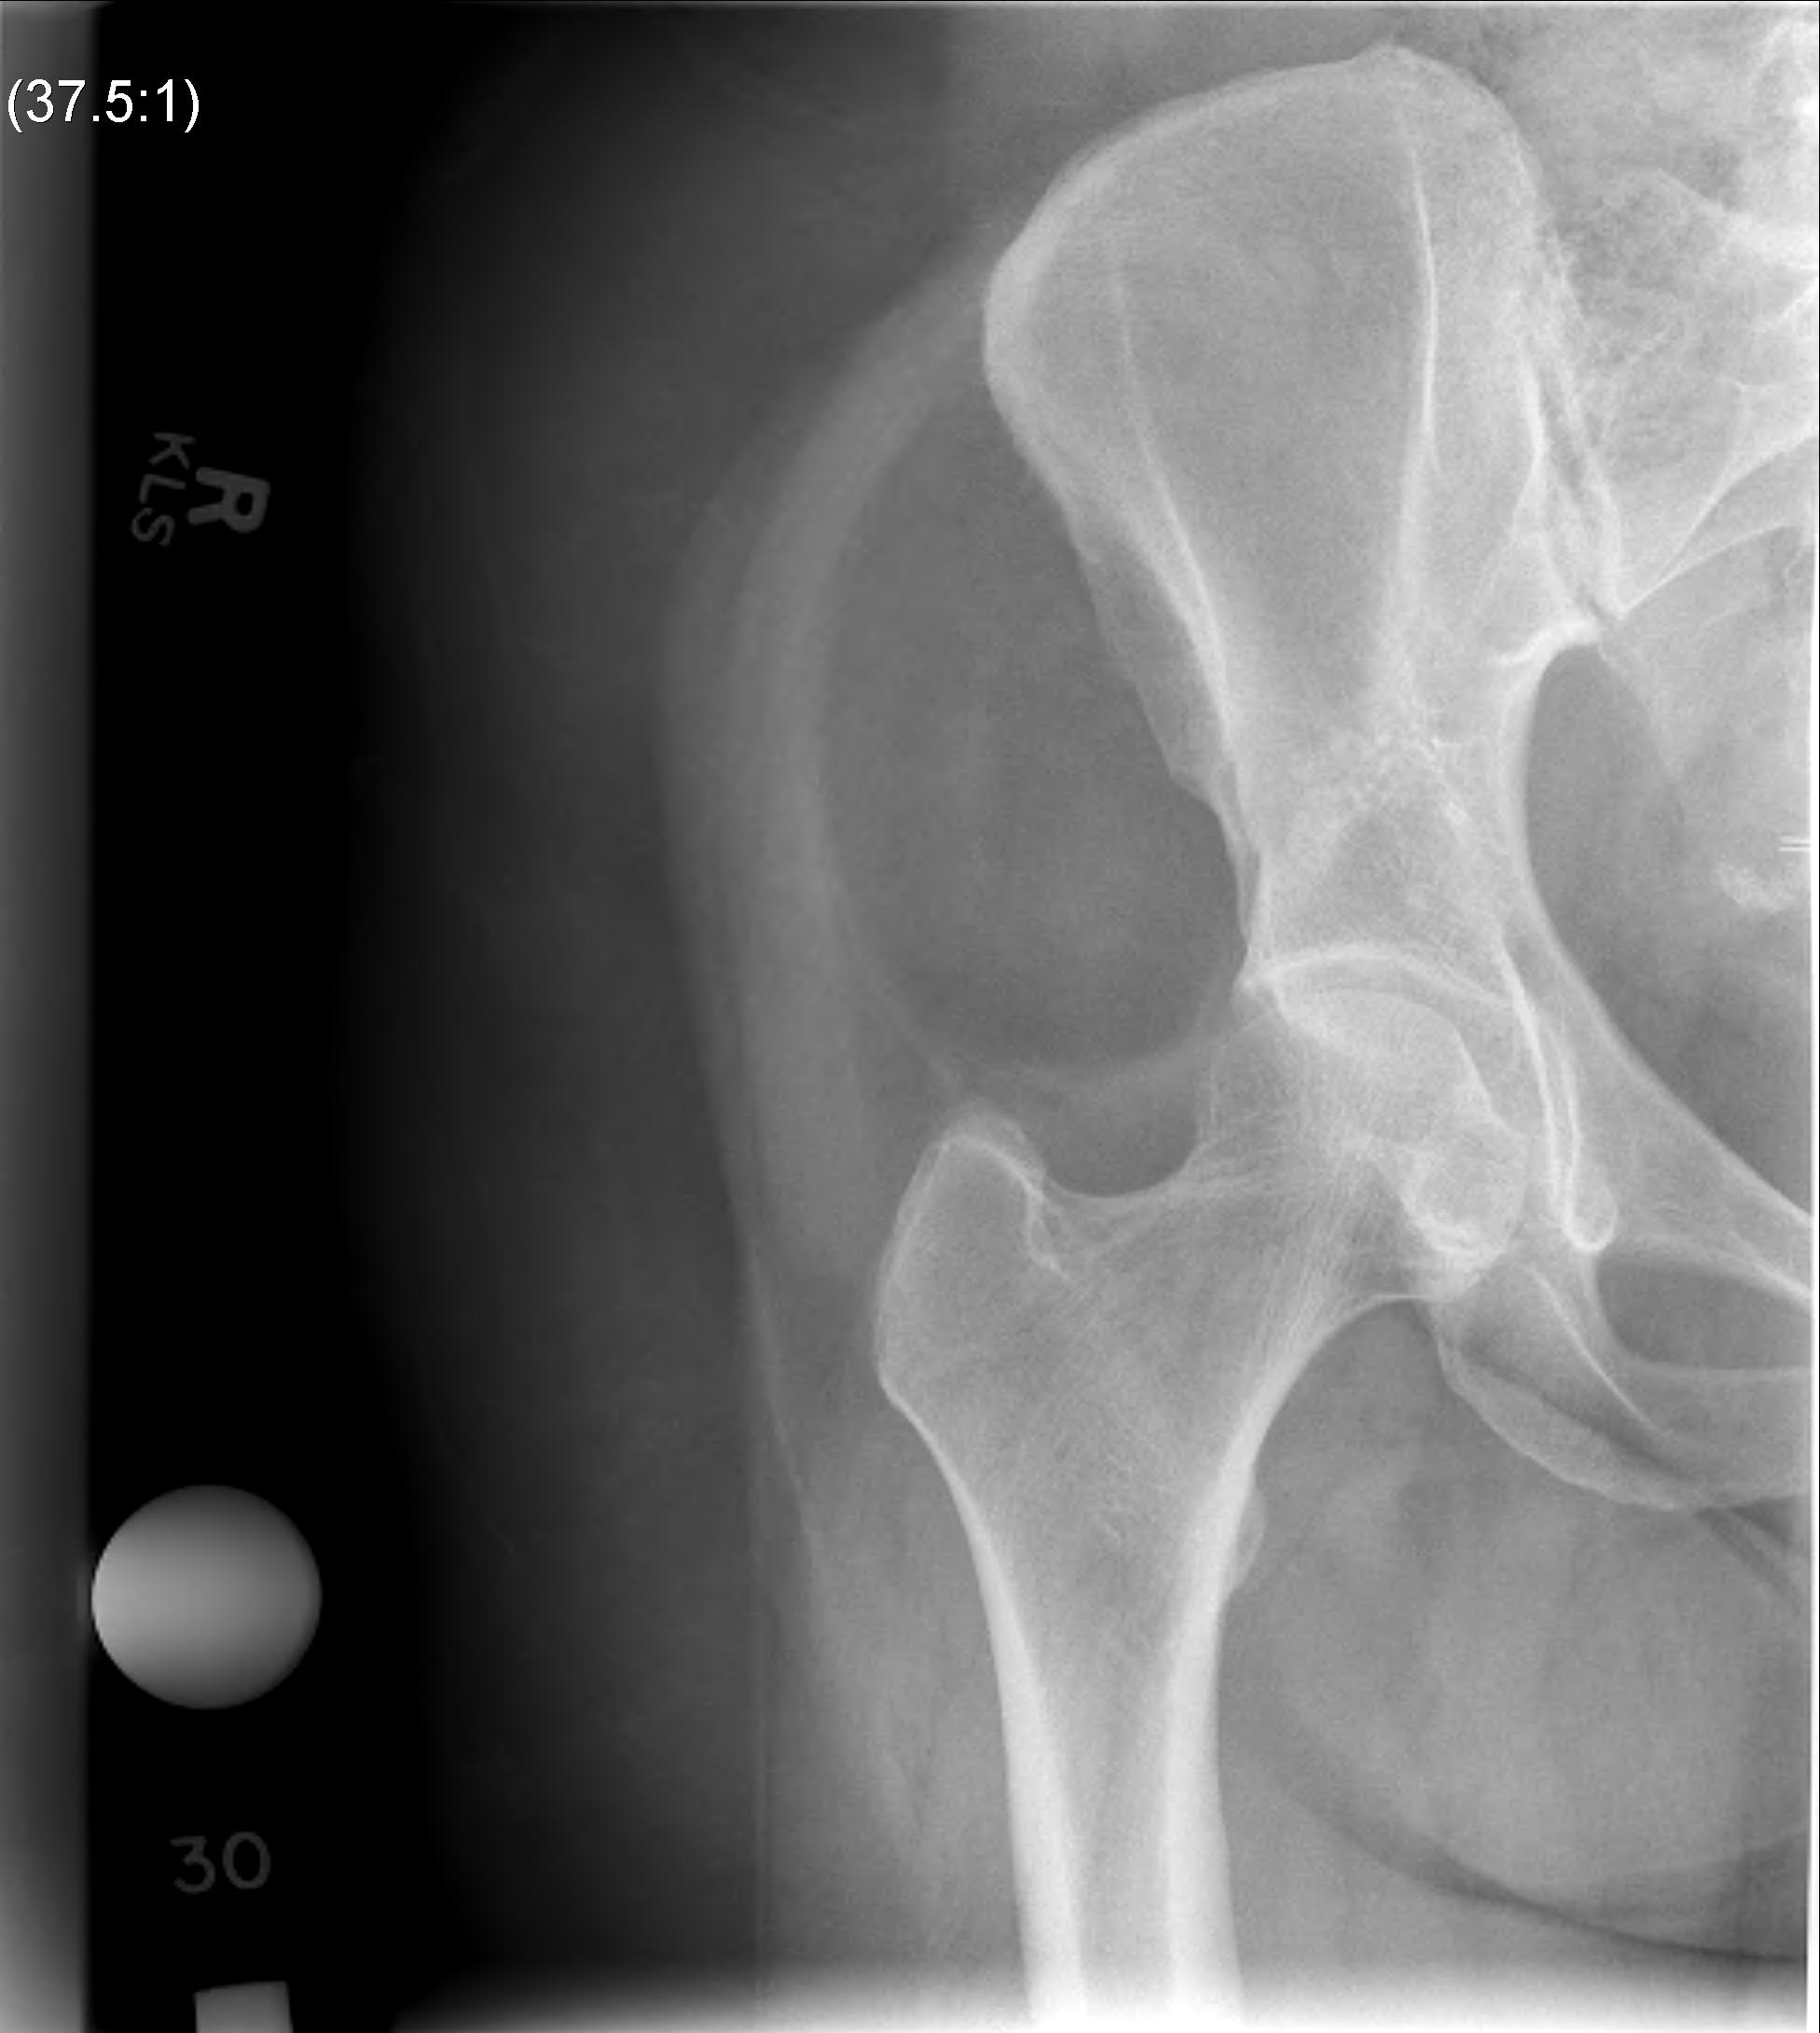

Liposarcoma

MRI

Deep to fascia / heterogenous

Liposarcoma pelvis